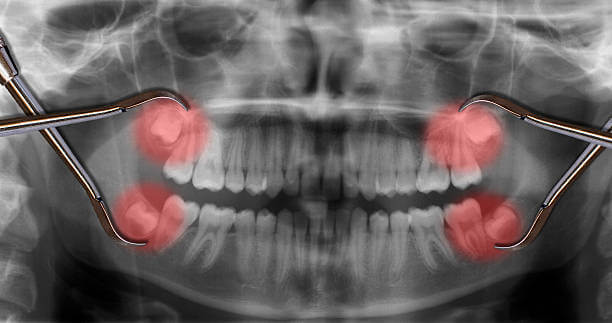

인류의 턱이 작아지면서 입안 깊숙이 사랑니가 자랄 공간이 부족해졌고 이 때문에 사랑니는 눕거나 발치하는 등 썩거나 염증이 생기기 쉬운 모양으로 나오는 경우가 많습니다.

사랑니는 다른 치아에 비해 크기와 모양이 매우 다양합니다. 사랑니는 똑바로 나오지 않고 기울어져 있거나 누워있는 경우 잇몸에 묻혀 있는 부분이 많습니다.

이 때문에 음식물 찌꺼기가 잇몸과 사랑니 사이에 끼기 쉽고 칫솔이 사랑니에 잘 닿지 않아 썩는 경우가 많고 제대로 청소하지 않으면 세균이 번식하고 염증이 생기기 쉬운 상태가 됩니다.